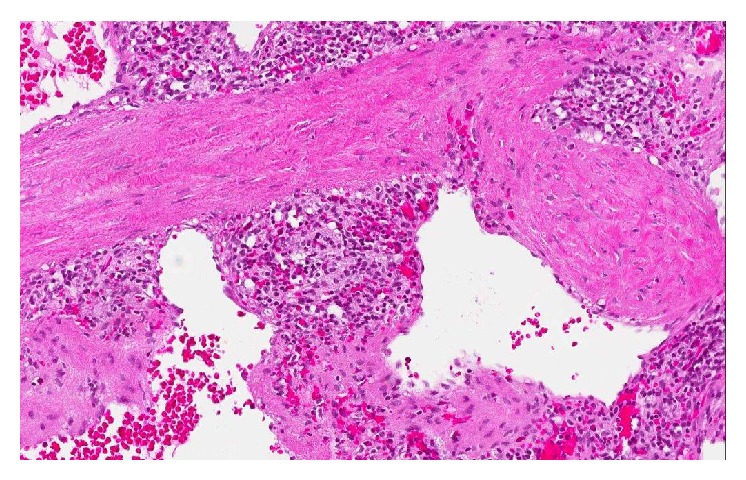

Metastasis of primary pancreatic adenocarcinoma to a small pulmonary artery (Courtesy Dr. V. Penopoulos)